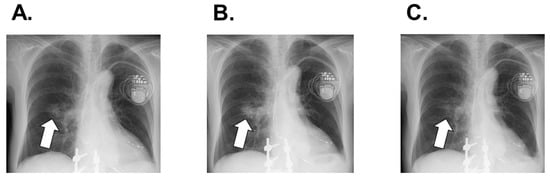

2.3. In-Hospital Course

2.4. Post-Discharge Course